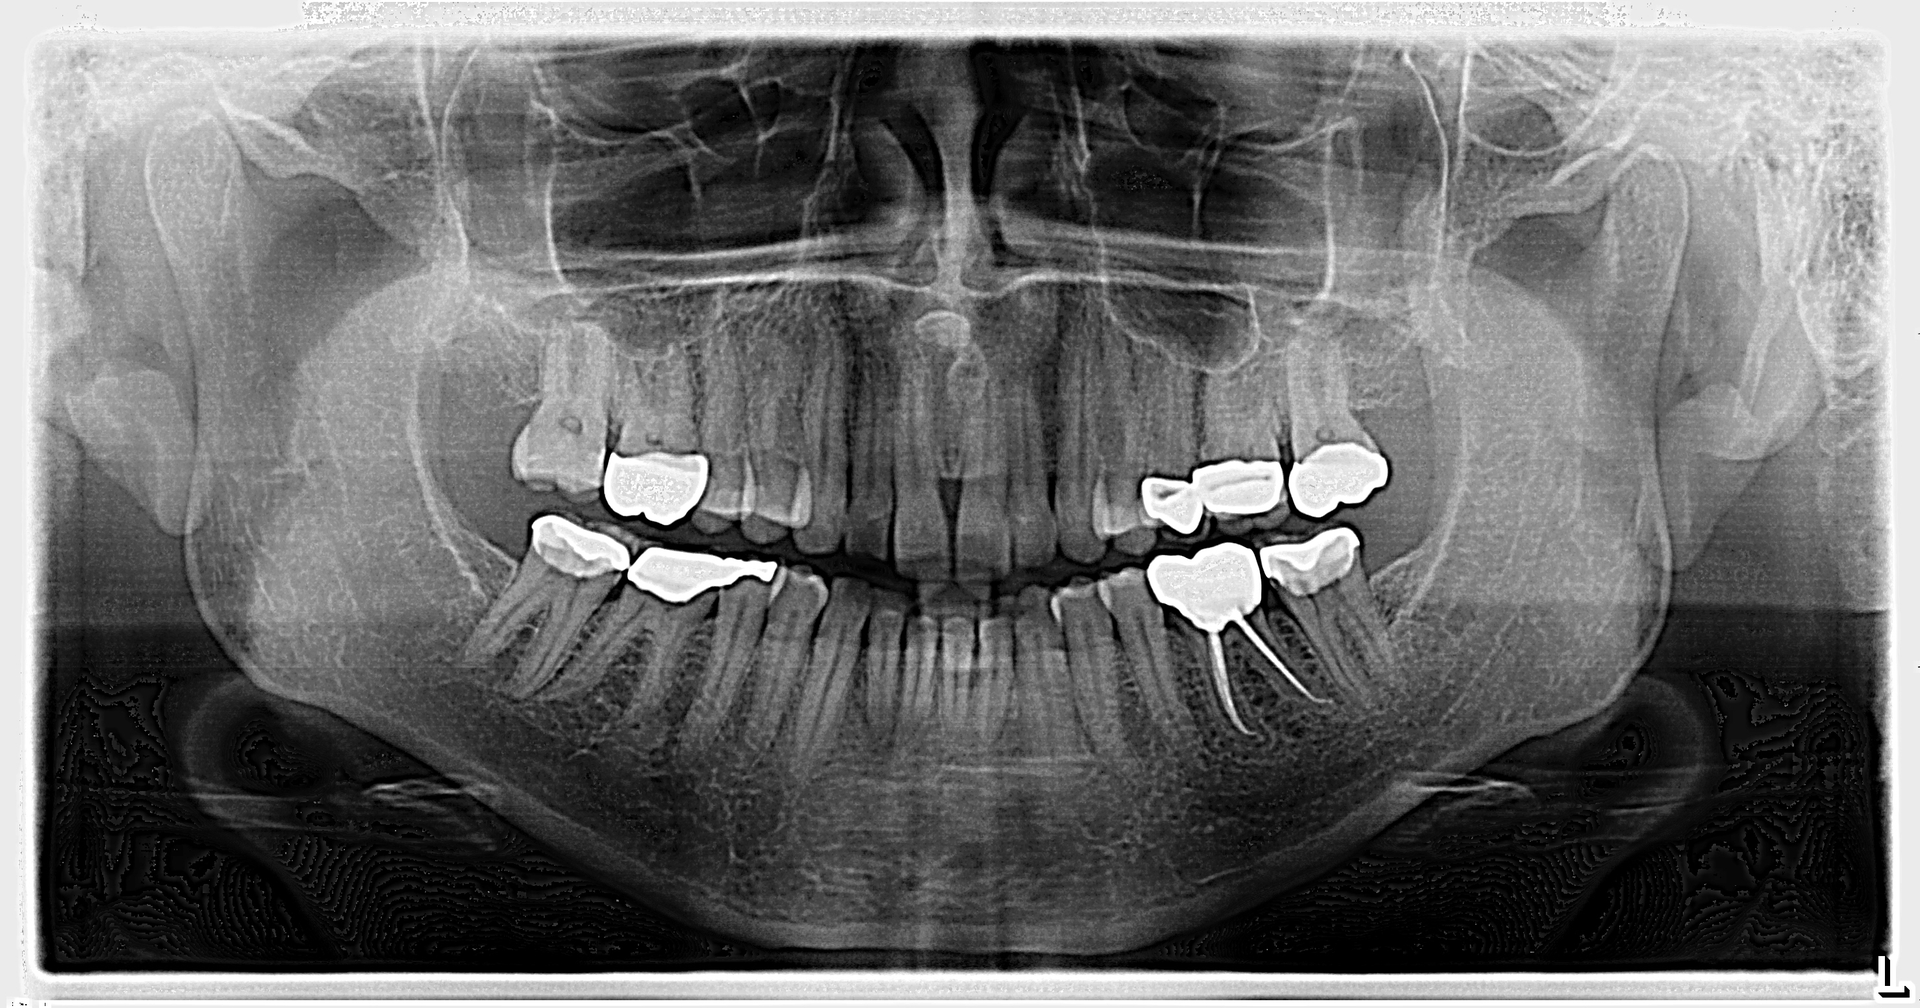

An assessment of the pan revealed two radiopaque lesions apical to the root tips of nos. 8 and 9, each measuring approximately 8 mm x 4 mm (figure 1). There was no tenderness on palpation in the generalized area. Access to a previous pan taken six years prior revealed no significant changes to the radiopacities (figure 2).

Given the location, absence of change, and shape of the lesions, the diagnosis for these lesions is mesiodens, a “supernumerary tooth located between the maxillary central incisors.”1 The lesions may occur “as single, multiple, unilateral, or bilateral (lesions); the presence of multiple supernumerary teeth is called ‘mesiodentes.’”2 By way of appearance, they typically manifest as a conical or peg-shaped form.2

Treatment of mesiodens varies. Although typically asymptomatic, they are “often extracted for aesthetic reasons, to allow the eruption of other teeth, orthodontic reasons, and/or suspected pathology.”3 In this particular case, the mesiodentes had been stable through the years without pathology or issues with regard to the patient’s permanent dentition. We will continue to monitor the patient via regular panoramic x-rays.